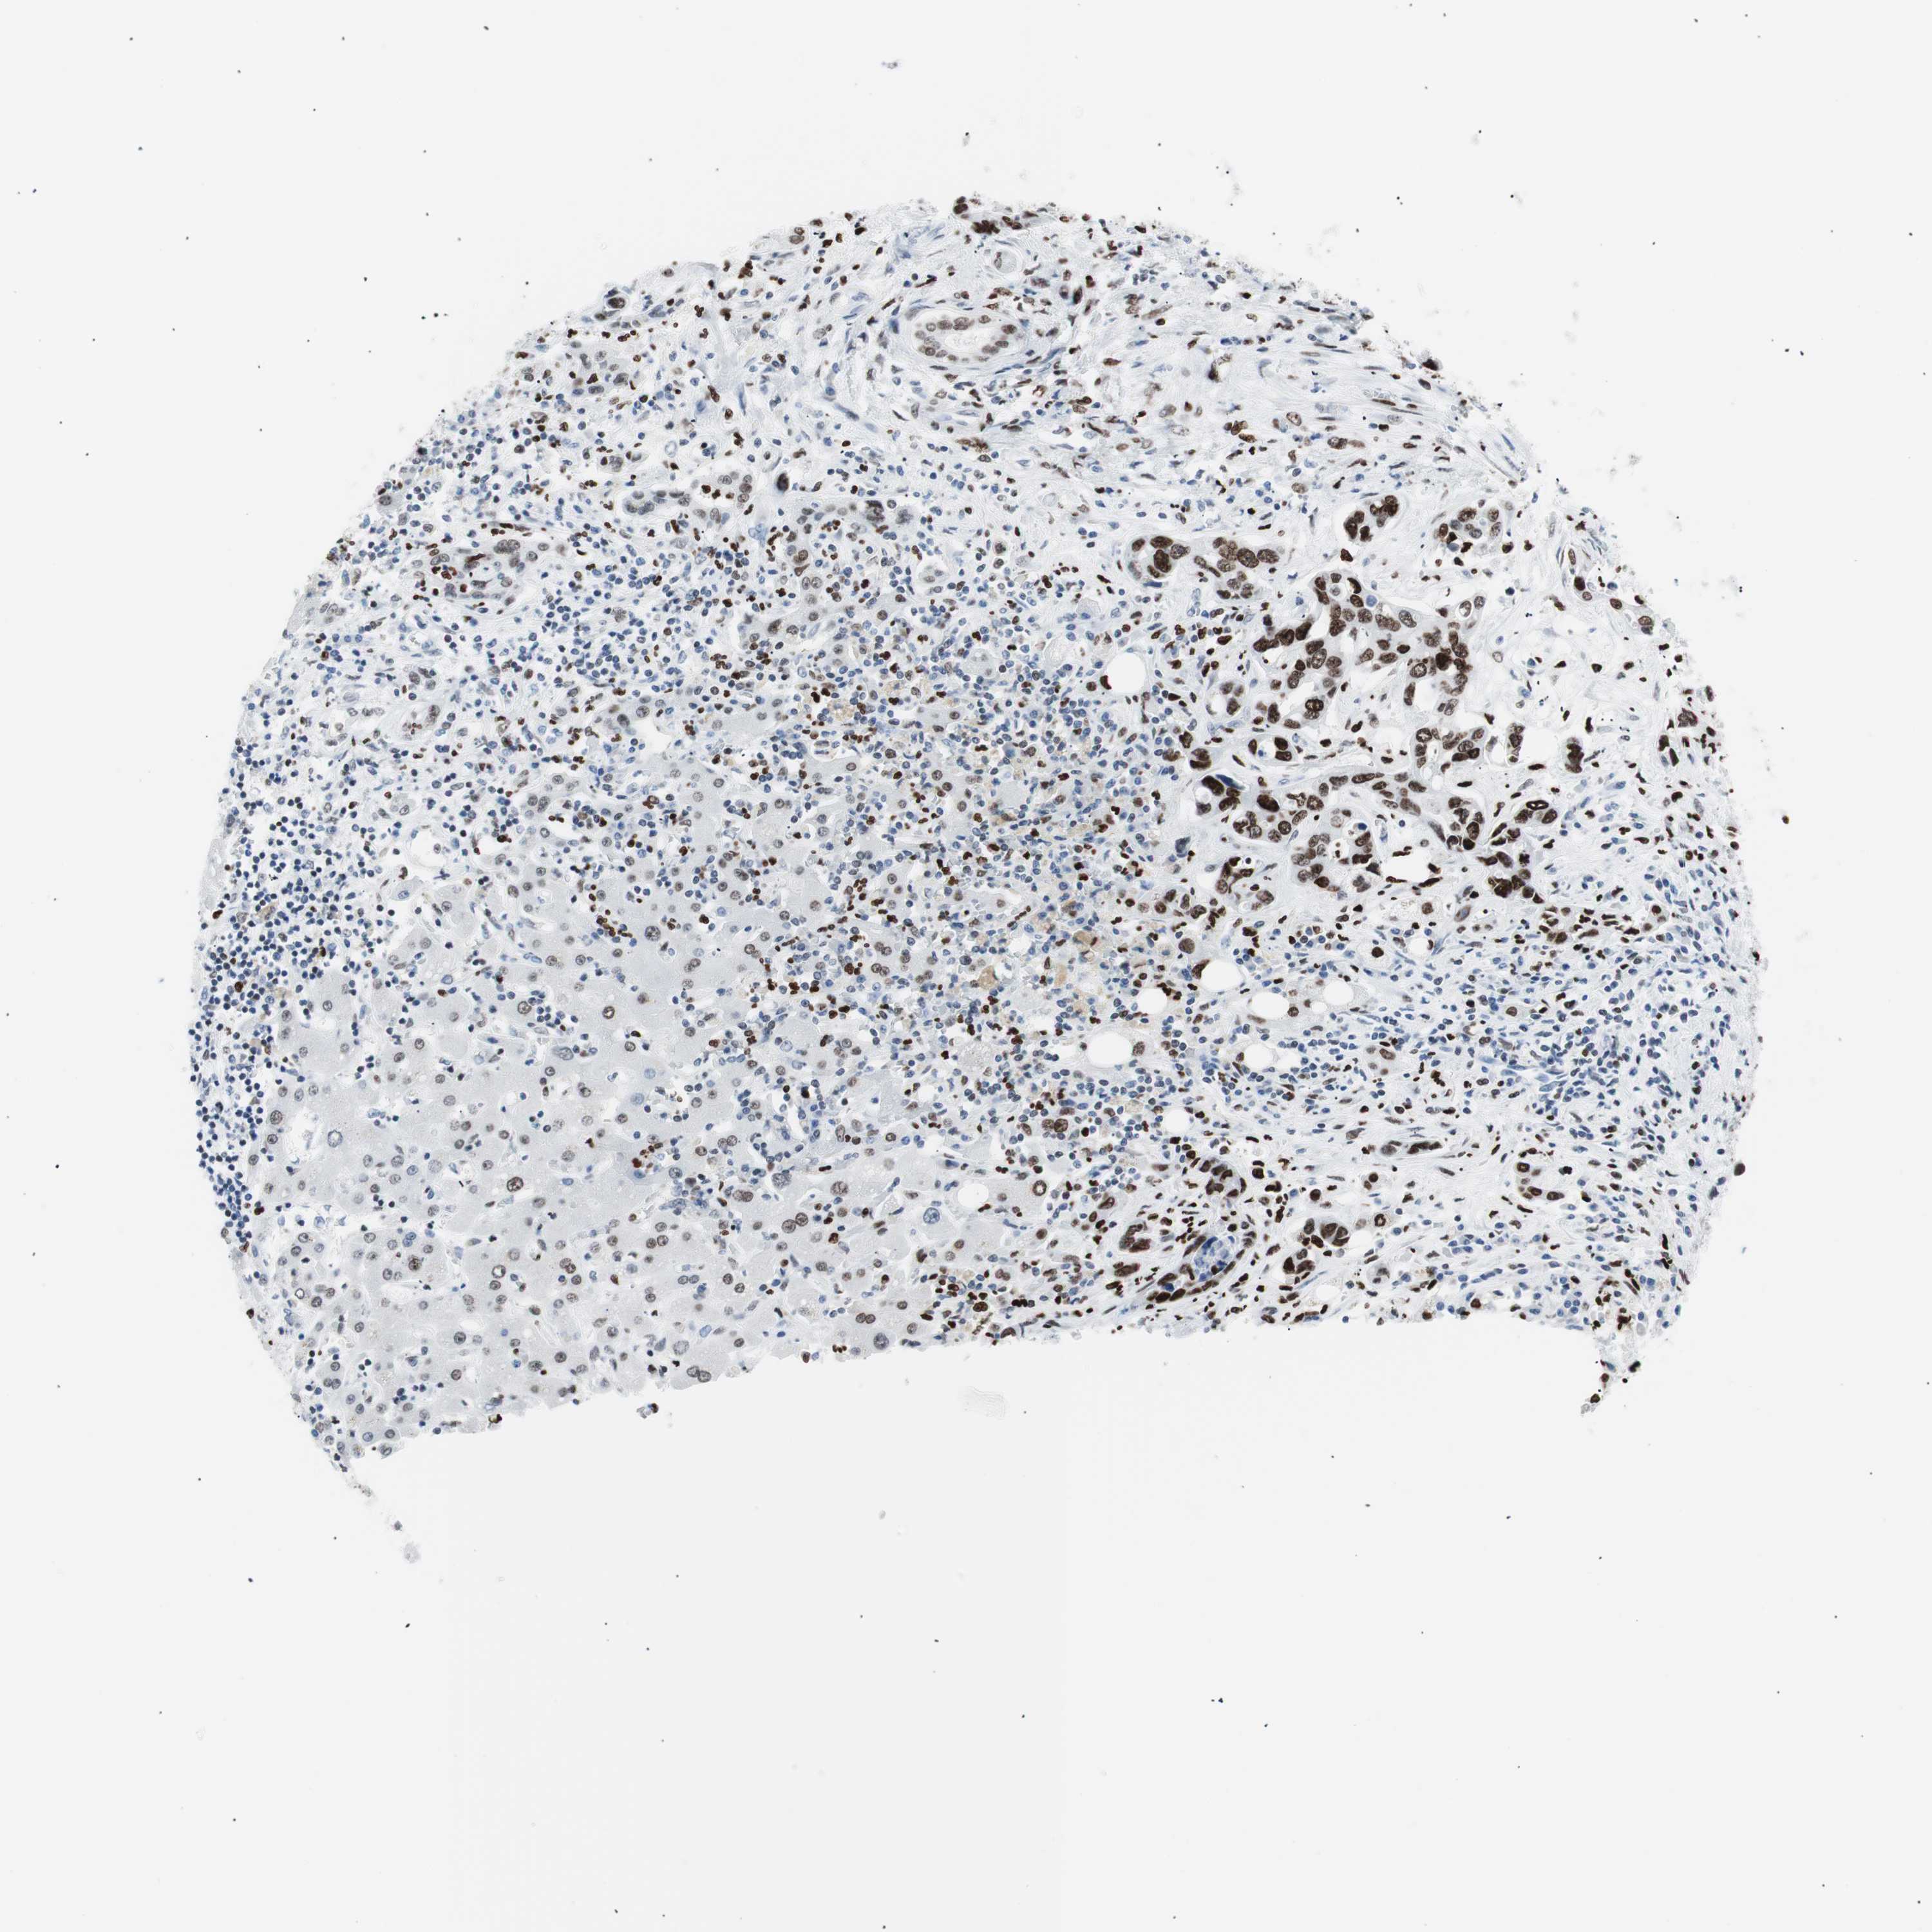

LIVER CANCER - Protein expressioni

A mouse-over function shows sample information and annotation data. Click on an image to view it in a full screen mode. Samples can be filtered based on level of antibody staining by selecting one or several of the following categories: high, medium, low and not detected. The assay and annotation is described here.

Note that samples used for immunohistochemistry by the Human Protein Atlas do not correspond to samples in the TCGA dataset.

Antibody stainingi

Antibody staining in the annotated cell types in the current human tissue is reported as not detected, low, medium, or high, based on conventional immunohistochemistry profiling in selected tissues. This score is based on the combination of the staining intensity and fraction of stained cells.

Each image is clickable and will lead to virtual microscopy that enables deeper exploration of all samples and also displays staining intensity scores, fraction scores and subcellular localization as well as patient and tissue information for each sample.

Antibody CAB004213

Staining

High

Medium

Low

Not detected

Intensity

Strong

Moderate

Weak

Negative

Quantity

>75%

75%-25%

<25%

None

Location

Nuclear

Cytoplasmic/membranous

Cytoplasmic/membranous,nuclear

Cholangiocarcinoma

Carcinoma, Hepatocellular, NOS